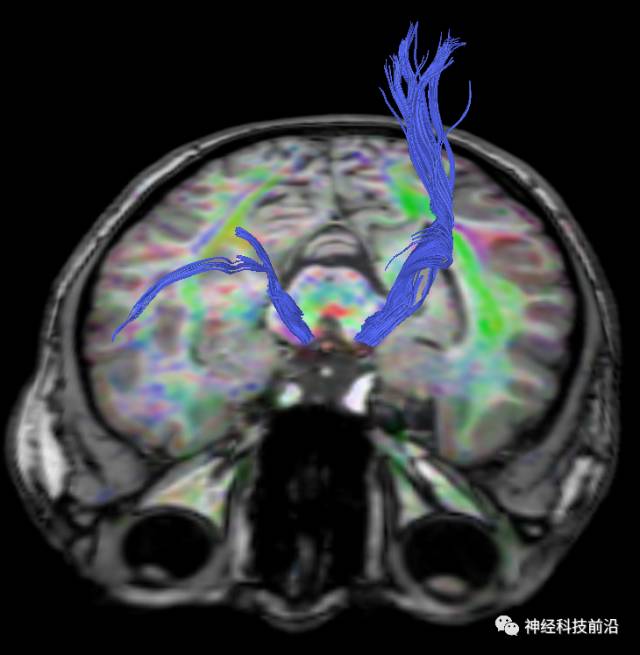

下面为皮质脑桥束的走形方位

皮质脑桥束与脑干高信号(黄色)纤维束

皮质脊髓束与皮质脑桥束的关系毗邻

终上所述:脑干高信号为一近环形纤维束,内囊后肢高信号为皮质脑桥束,皮质脊髓束在中脑位置略靠后。高信号位于中脑前缘,是皮质脑桥束的位置所在,另外有部分桥连纤维。